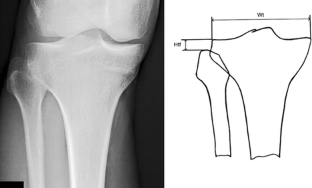

Fig. 2